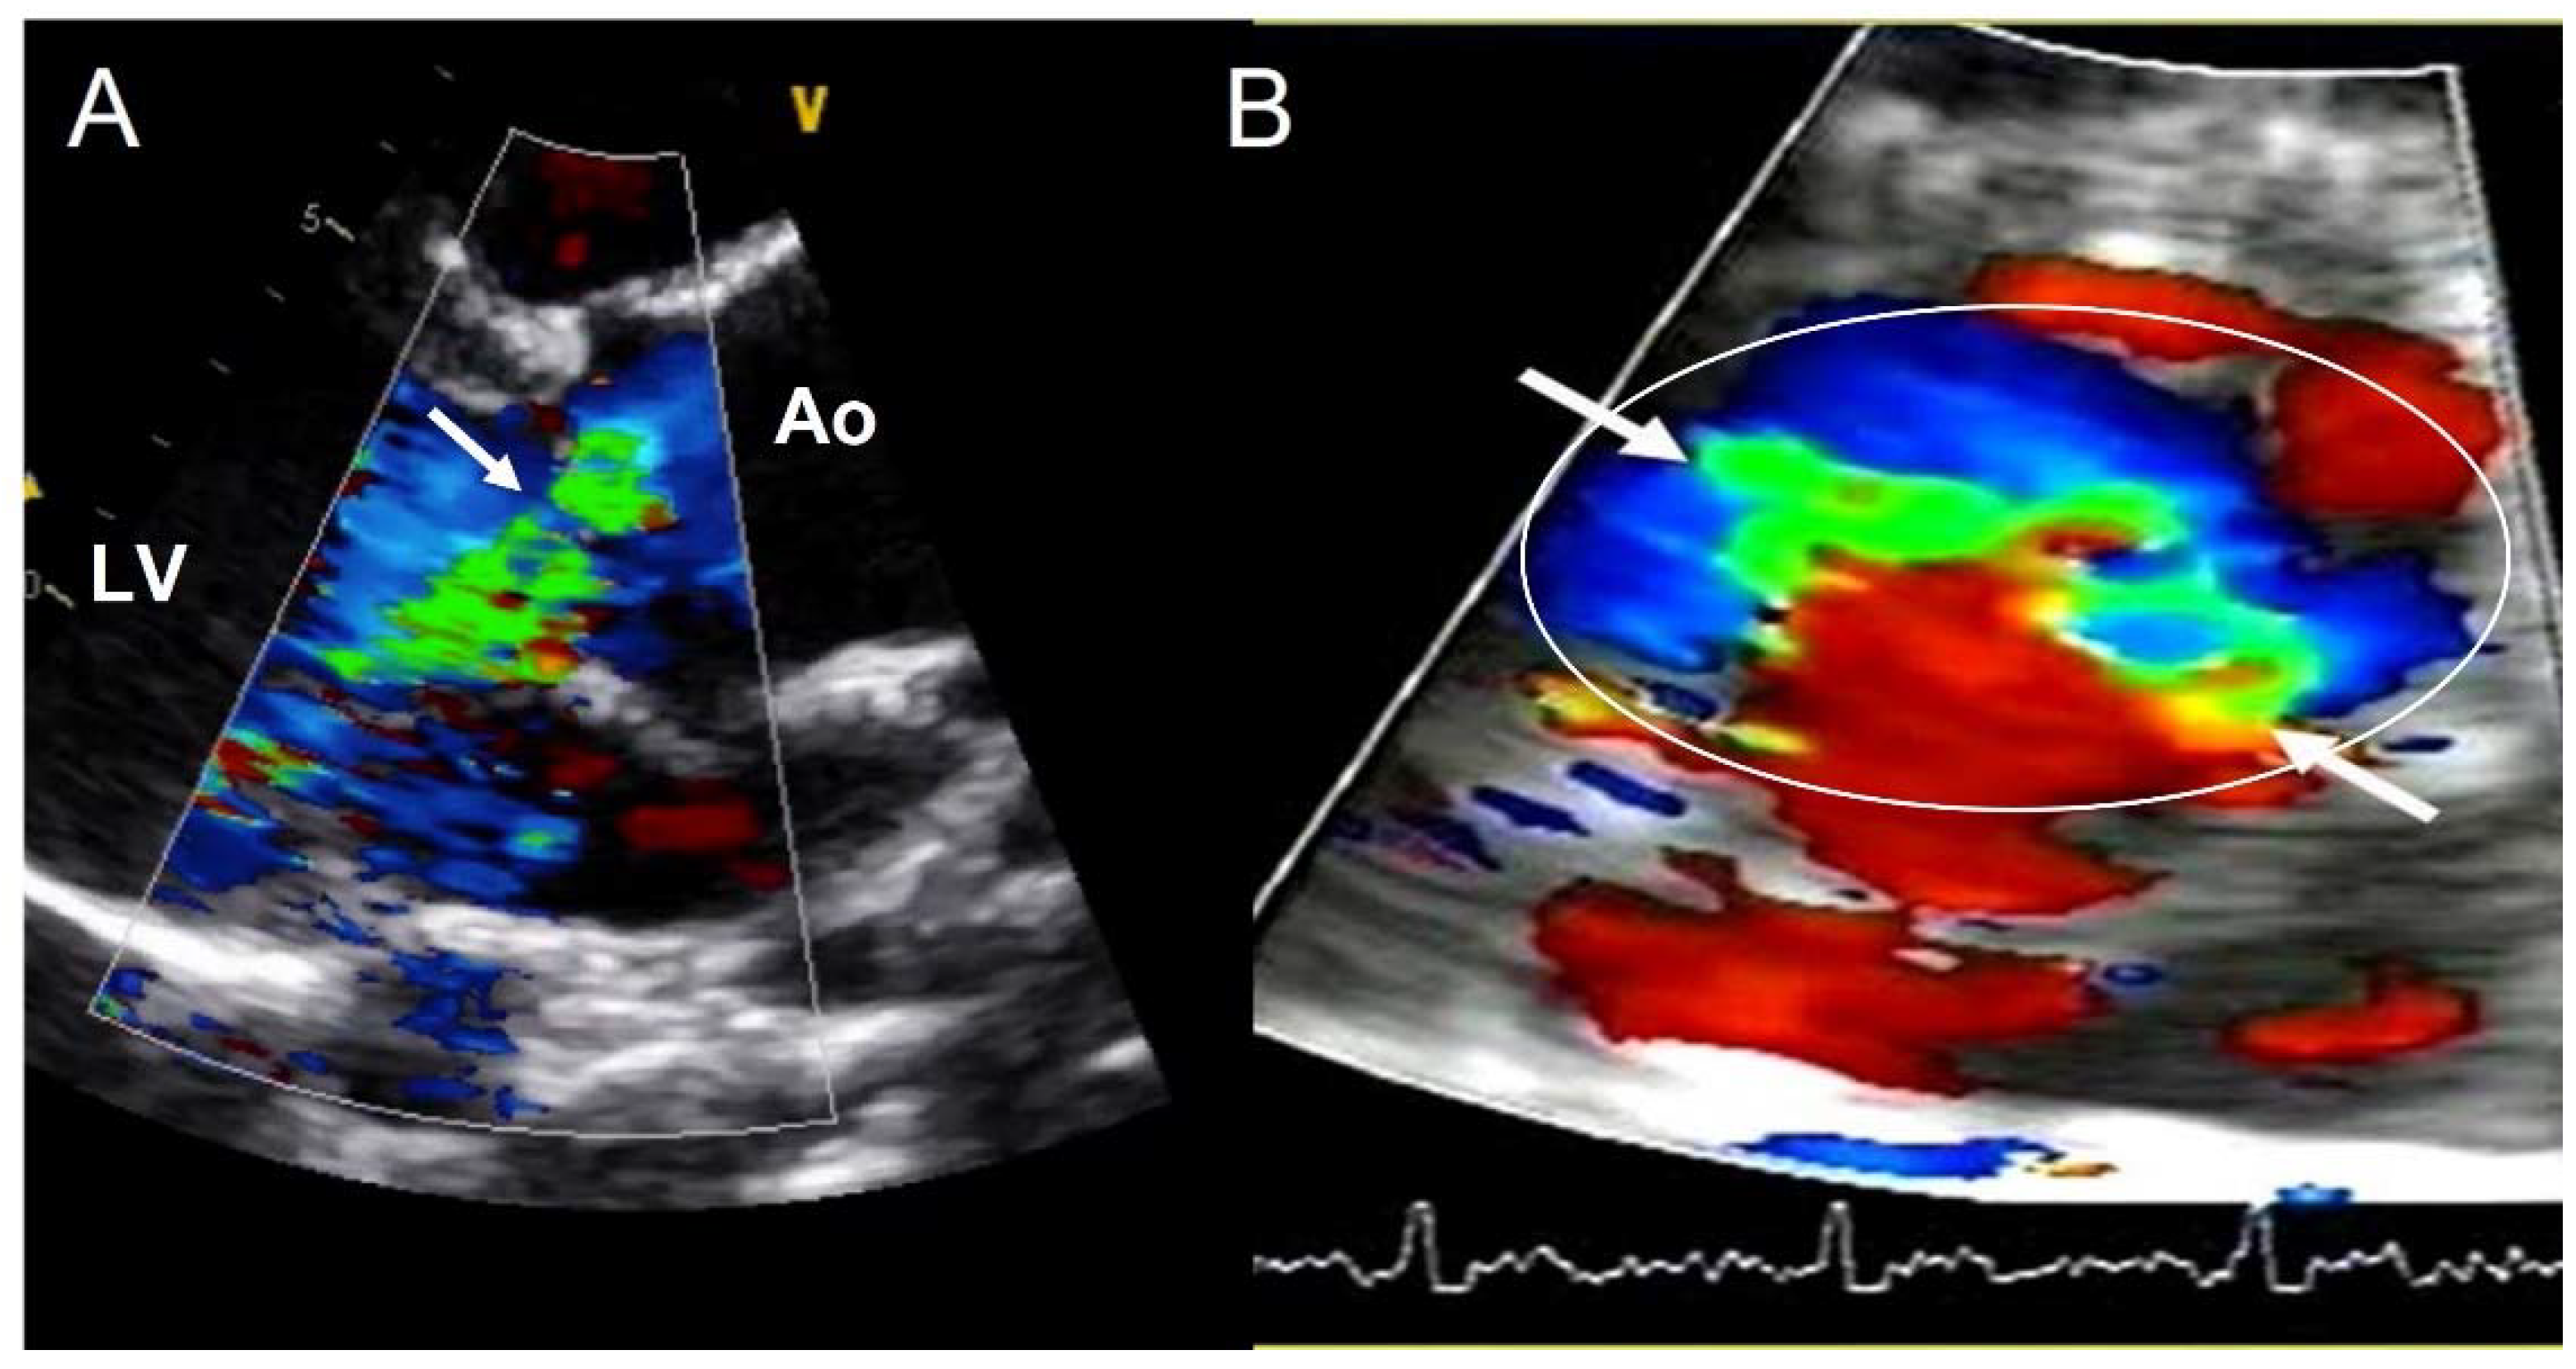

Valvular dysfunction as AR is more frequent in younger patients, but also in males [41]. Although its prevalence ranges between 47% and 64%, moderate−severe grade appears in less than 30% of individuals [9,32,33,34,35,42]. Annular dilation and cusp prolapse or retraction is the most common underlying cause of chronic regurgitation, acting either alone or in combination [43]. The evaluation of AR severity in BAV by TTE is challenging, given that eccentric jets are common. In some cases, CMR may be superior to TTE for quantifying AR (Figure 5) [44,45]. The CMR phase contrast is accurate and reproducible in AR assessment with the estimation of the regurgitant volume and regurgitant fraction. We labelled a regurgitant fraction of more than 30% as severe [46].

Figure 5.

Severe aortic regurgitation in a BAV. (A) Eccentric jet in parasternal long axis-view (arrow). (B) The short-axis view shows the elliptic shape of the regurgitant orifice (arrows) in the aortic annulus (circle). Ao—aorta; LV—left ventricle.